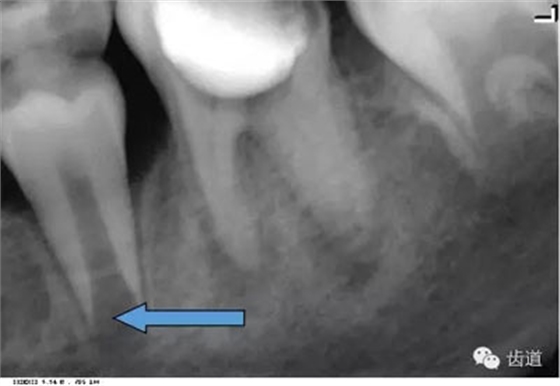

4)外斜線:

由升支前緣下部斜向前下方,為一密度高的帶狀影像。常重疊在第二、三磨牙牙冠處、頸部或根部,使牙髓室或根管不能清晰顯示